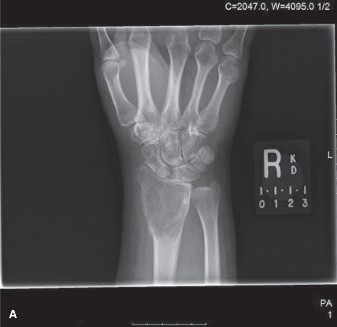

A 40-year-old male presents with complaint of pain and swelling at the right wrist for 3 months. He works as …